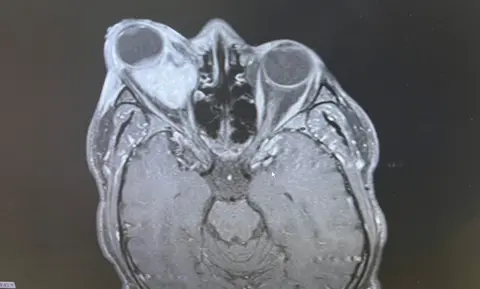

Collect/PA Real LifeAfter having a scan, Mr Oladapo was told by doctors that a mass was causing his eye to protrude and he said a biopsy during surgery on 10 June revealed it was a cancerous tumour, specifically embryonal rhabdomyosarcoma – a type of soft tissue cancer.